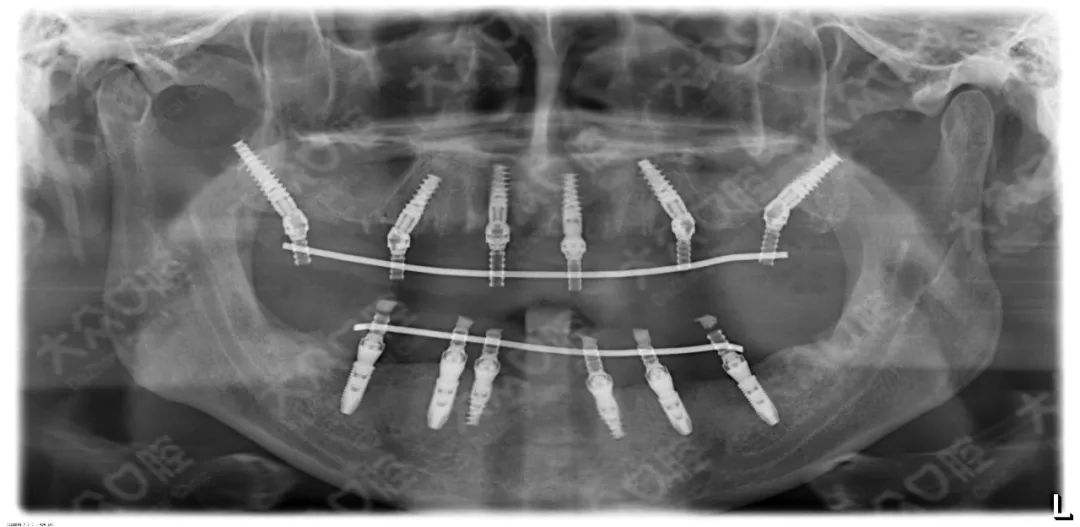

3、種植修復(fù)

適用于:各種多顆牙、半口牙甚至全口牙齒的缺失。

優(yōu)點:恢復(fù)咀嚼功能最多的修復(fù)方式,屬于固定修復(fù),不能自行取下。

缺點:費(fèi)用較高,修復(fù)周期較長,有些還需要植骨。修復(fù)周期從拔牙算起得半年以上的時間。